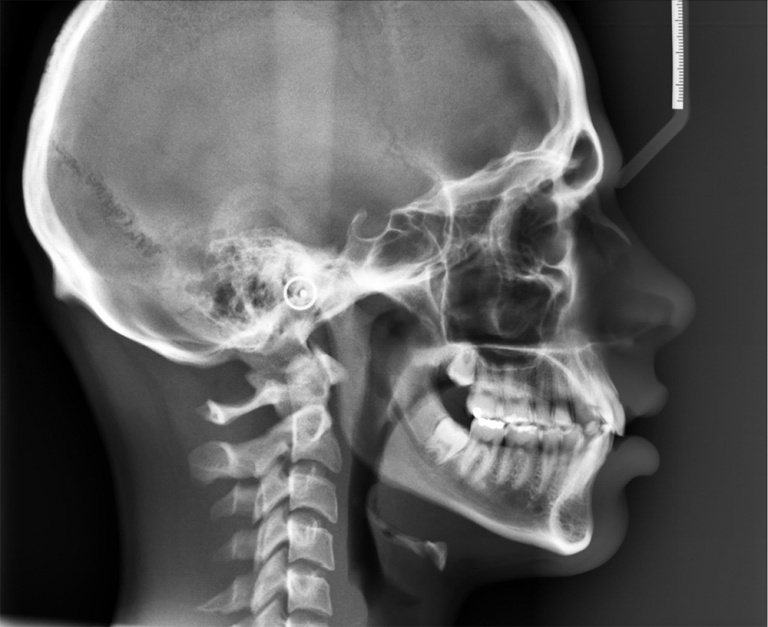

WebRadiografía de la columna torácica. Es una radiografía de los 12 huesos (vértebras) del tórax (torácicos) de la columna vertebral. Las vértebras están separadas por. WebUna telerradiografía de cráneo es una radiografía de la cara del paciente, realizada a mayor distancia de lo habitual: de ahí el prefijo “tele-”. Esta espacio adicional (el.

WebRAYOS X ANTEBRAZO AP Y LATERAL - 2. Para este estudio no se requiere cita. Consulta a tu Médico y recuerda que él es quien debe prescribir e interpretar los estudios. Los. WebLa medición ideal se realiza con TAC y valora la rotación entre el cuello femoral y los cóndilos femorales. Se mide mediante cortes axiales, que se superponen. Uno sobre el. WebRadiografía de columna es un estudio que permite conocer el estado de la columna completamente por medio de Rayos X, agenda tu cita hoy mismo. Radiografía de. WebLa radiografía de columna lumbar AP y lateral es el primer paso en el algoritmo diagnóstico. También suele iniciar la secuencia diagnóstica en pacientes con síntomas referidos a la. WebTelerradiología columna. Técnica mediante la cual, utilizando rayos X, se obtienen imágenes de toda la columna vertebral para su estudio, valorando especialmente la. WebTELERRADIOGRAFIA MIEMBROS INFERIORES CARACTERISTICAS KV: BAJO Tiempo de corto Punto focal fino Distancia COLIMACION: borde superior de las crestas iliacas. WebLa telerradiografía de cráneo es una técnica radiográfica extraoral mediante la cual se obtiene una vista del cráneo y las estructuras óseas de la cara en formato digital. Se. WebTelerradiografía de Columna o Miembros Inferiores en Madrid Resona al precio de 70€ | ClinicPoint. sin cuotas mensuales Los mejores médicos y centros Sin listas de espera..

WebLa telerradiografía de cráneo es una técnica radiográfica extraoral mediante la cual se obtiene una vista del cráneo y las estructuras óseas de la cara en formato digital. Se. WebTelerradiografía de Columna o Miembros Inferiores en Madrid Resona al precio de 70€ | ClinicPoint. sin cuotas mensuales Los mejores médicos y centros Sin listas de espera.. WebLas técnicas radiológicas para el estudio de la columna dorsal y lumbar se realizan para distinguir escoliosis y normalmente constituyen una serie de varias.